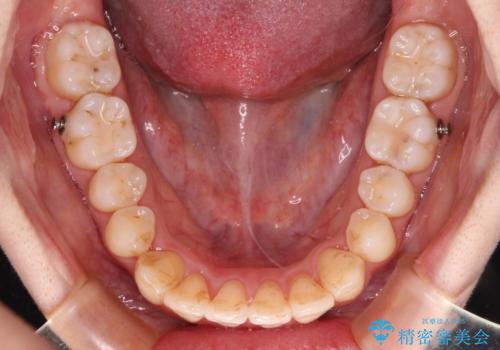

【モニター】前歯の前突感とクロスバイトをインビザラインで改善

インビザラインで歯列を移動する前に、上顎前歯をワイヤー矯正で整え、その後上下歯列をインビザラインにて矯正治療を行うこととしました。

舌側転位している側切歯特有の、切縁の位置が不揃いであったり、根元が内側に引っ込んだ状態であったりという、インビザライン独特の仕上がりになることなく、きれいに整った歯列とすることができました。